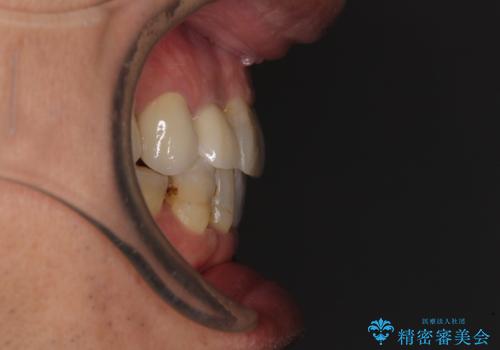

- 前歯のデコボコや、奥歯を咬んだときに痛みがあるとのことで来院された患者様です。

全体的に問題が多く、全てをしっかりと治療したいとのことでした。

全体的に中等度の歯周病と診断されたため、歯周外科処置やインプラントによる咬合回復から進めて行き、矯正治療による歯列改善を行った後にオールセラミッククラウンにて補綴することとしました。

矯正治療を希望して来院されましたが、歯周病を併発していたため、矯正治療開始前の処置が非常に多くなりました。特に歯槽骨の再生治療を行ったため、外科処置後の静置期間が長くなり、4年弱の治療期間となりました。